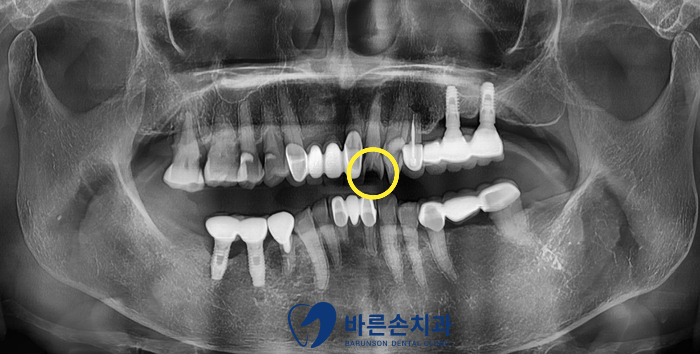

노란 동그라미 치아를 보시면

치아가 완전한 모양이 아니고 검은색으로 파여있는게 보이실까요??

구강 내 사진으로 다시 확인해보겠습니다.

엑스레이 사진에도 보였듯이 치아가 많이 깨져있는 상태입니다..

일단은 치아를 다듬어서 크라운만 해보자는 계획이었고

다듬는 중에 너무 신경과 가까우면 신경치료 가능성이 있다고 설명드렸습니다.

다행히도 신경이 드러나거나 하지 않아서!!

레진코어 후 크라운이 가능했습니다.